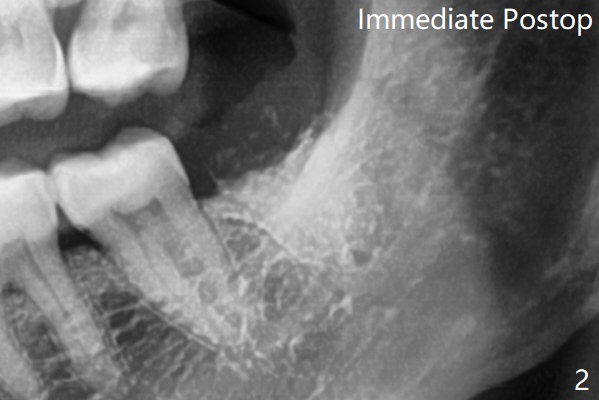

术前外斜脊(图一:*)存在,术后即刻没有消失,放置0.5毫升骨水泥(图二)。